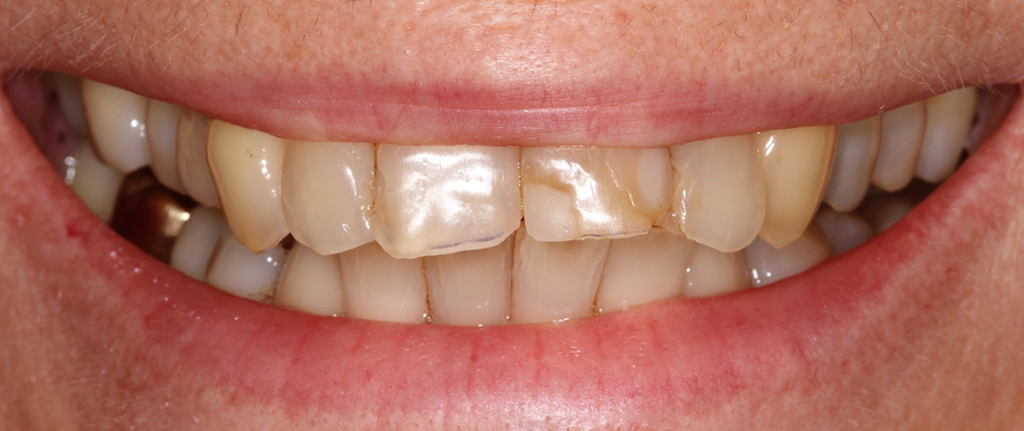

Die SäureÄtzTechnik macht es möglich, eine feste Verbindung zwischen der verbleibenden Zahnsubstanz und dem Compositmaterial zu erreichen Auch mit minimalinvasiven Präparationstechniken kann stabil restauriert werden Die neuesten Füllungsmaterialien sind ausserdem in puncto Ästhetik und Langlebigkeit sehr gut KeramikFüllungen. Die SäureÄtzTechnik macht es möglich, eine feste Verbindung zwischen der verbleibenden Zahnsubstanz und dem Compositmaterial zu erreichen Auch mit minimalinvasiven Präparationstechniken kann stabil restauriert werden Die neuesten Füllungsmaterialien sind ausserdem in puncto Ästhetik und Langlebigkeit sehr gut. Sie werden mittels eines speziellen Klebers mit Hilfe der SäureÄtzTechnik eingegliedert und erlauben so eine vollständig randdichte, passgenaue und somit kariesgeschützte Verbindung zwischen Zahn und Inlay Ferner können keramische Arbeiten durch individuelle Farbgebung der Oberfläche optimal an die vorhandene Zahnfarbe angepasst werden.

Auch Klebetechnik oder SäureÄtzTechnik (SÄT) genannt, ist eine Methode zur Befestigung von Zahnersatz in der Zahnmedizin Die Adhäsivtechnik wird sowohl bei KompositFüllungen und beim Zementieren von Keramikfüllungen als auch beim Befestigen von Kronen, Verblendschalen (Veneer) und Klebebrücken mittels Komposit sowie bei der. Ätzen von Schmelz und Dentin im Rahmen der SäureÄtzTechnik Enthält 34 %ige Phosphorsäure In kräftiger ab 34,19 € Lieferbar iBOND® Etch Gel Ätzen von Schmelz und Dentin für die ÄtzBondTechnik Vorteile Enthält ab 11,59 € Eingeschränkt lieferbar. Das Verfahren selbst wird SäureÄtzTechnik (SÄT) genannt Durch die Mikroretention wird die Dichtigkeit einer Füllung erheblich erhöht Sie führte erst zum vertretbaren Einsatz von Kunststoffen in der restaurativen Zahnmedizin Systematik Die Mikroretention wird folgendermaßen erreicht.